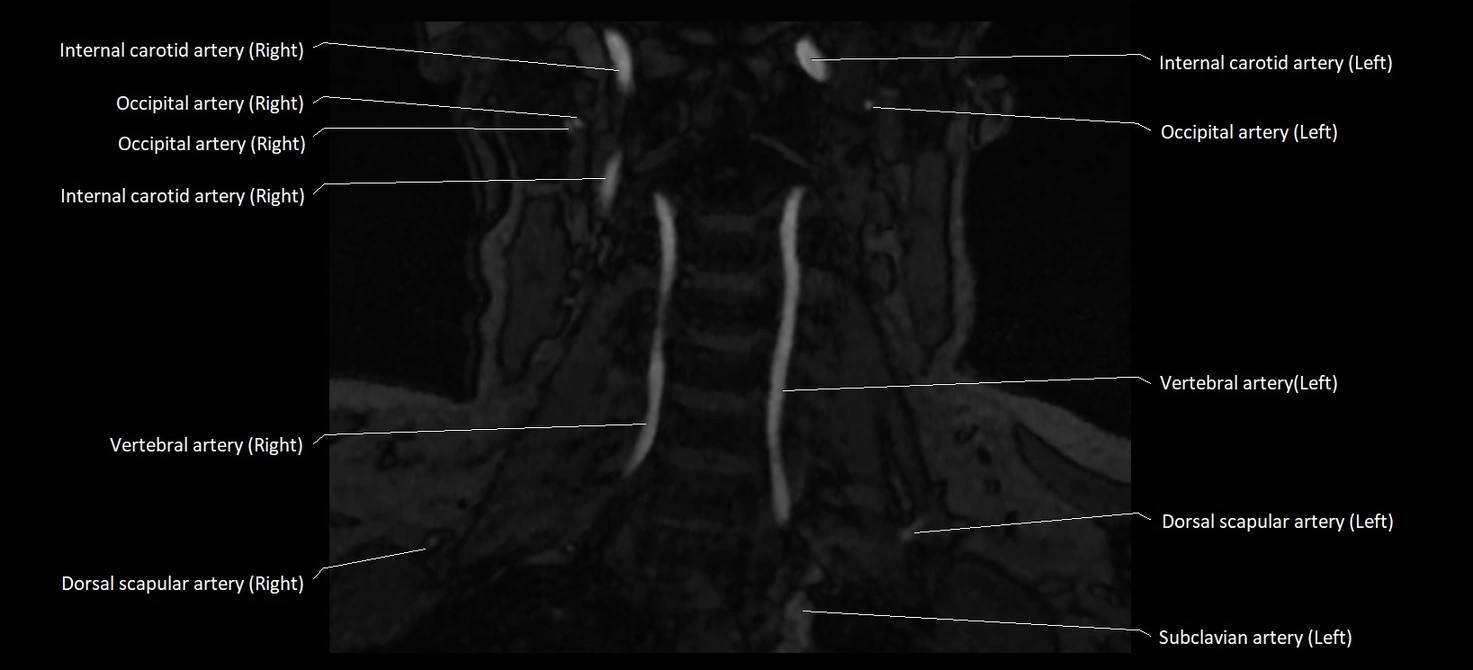

MRI images

image